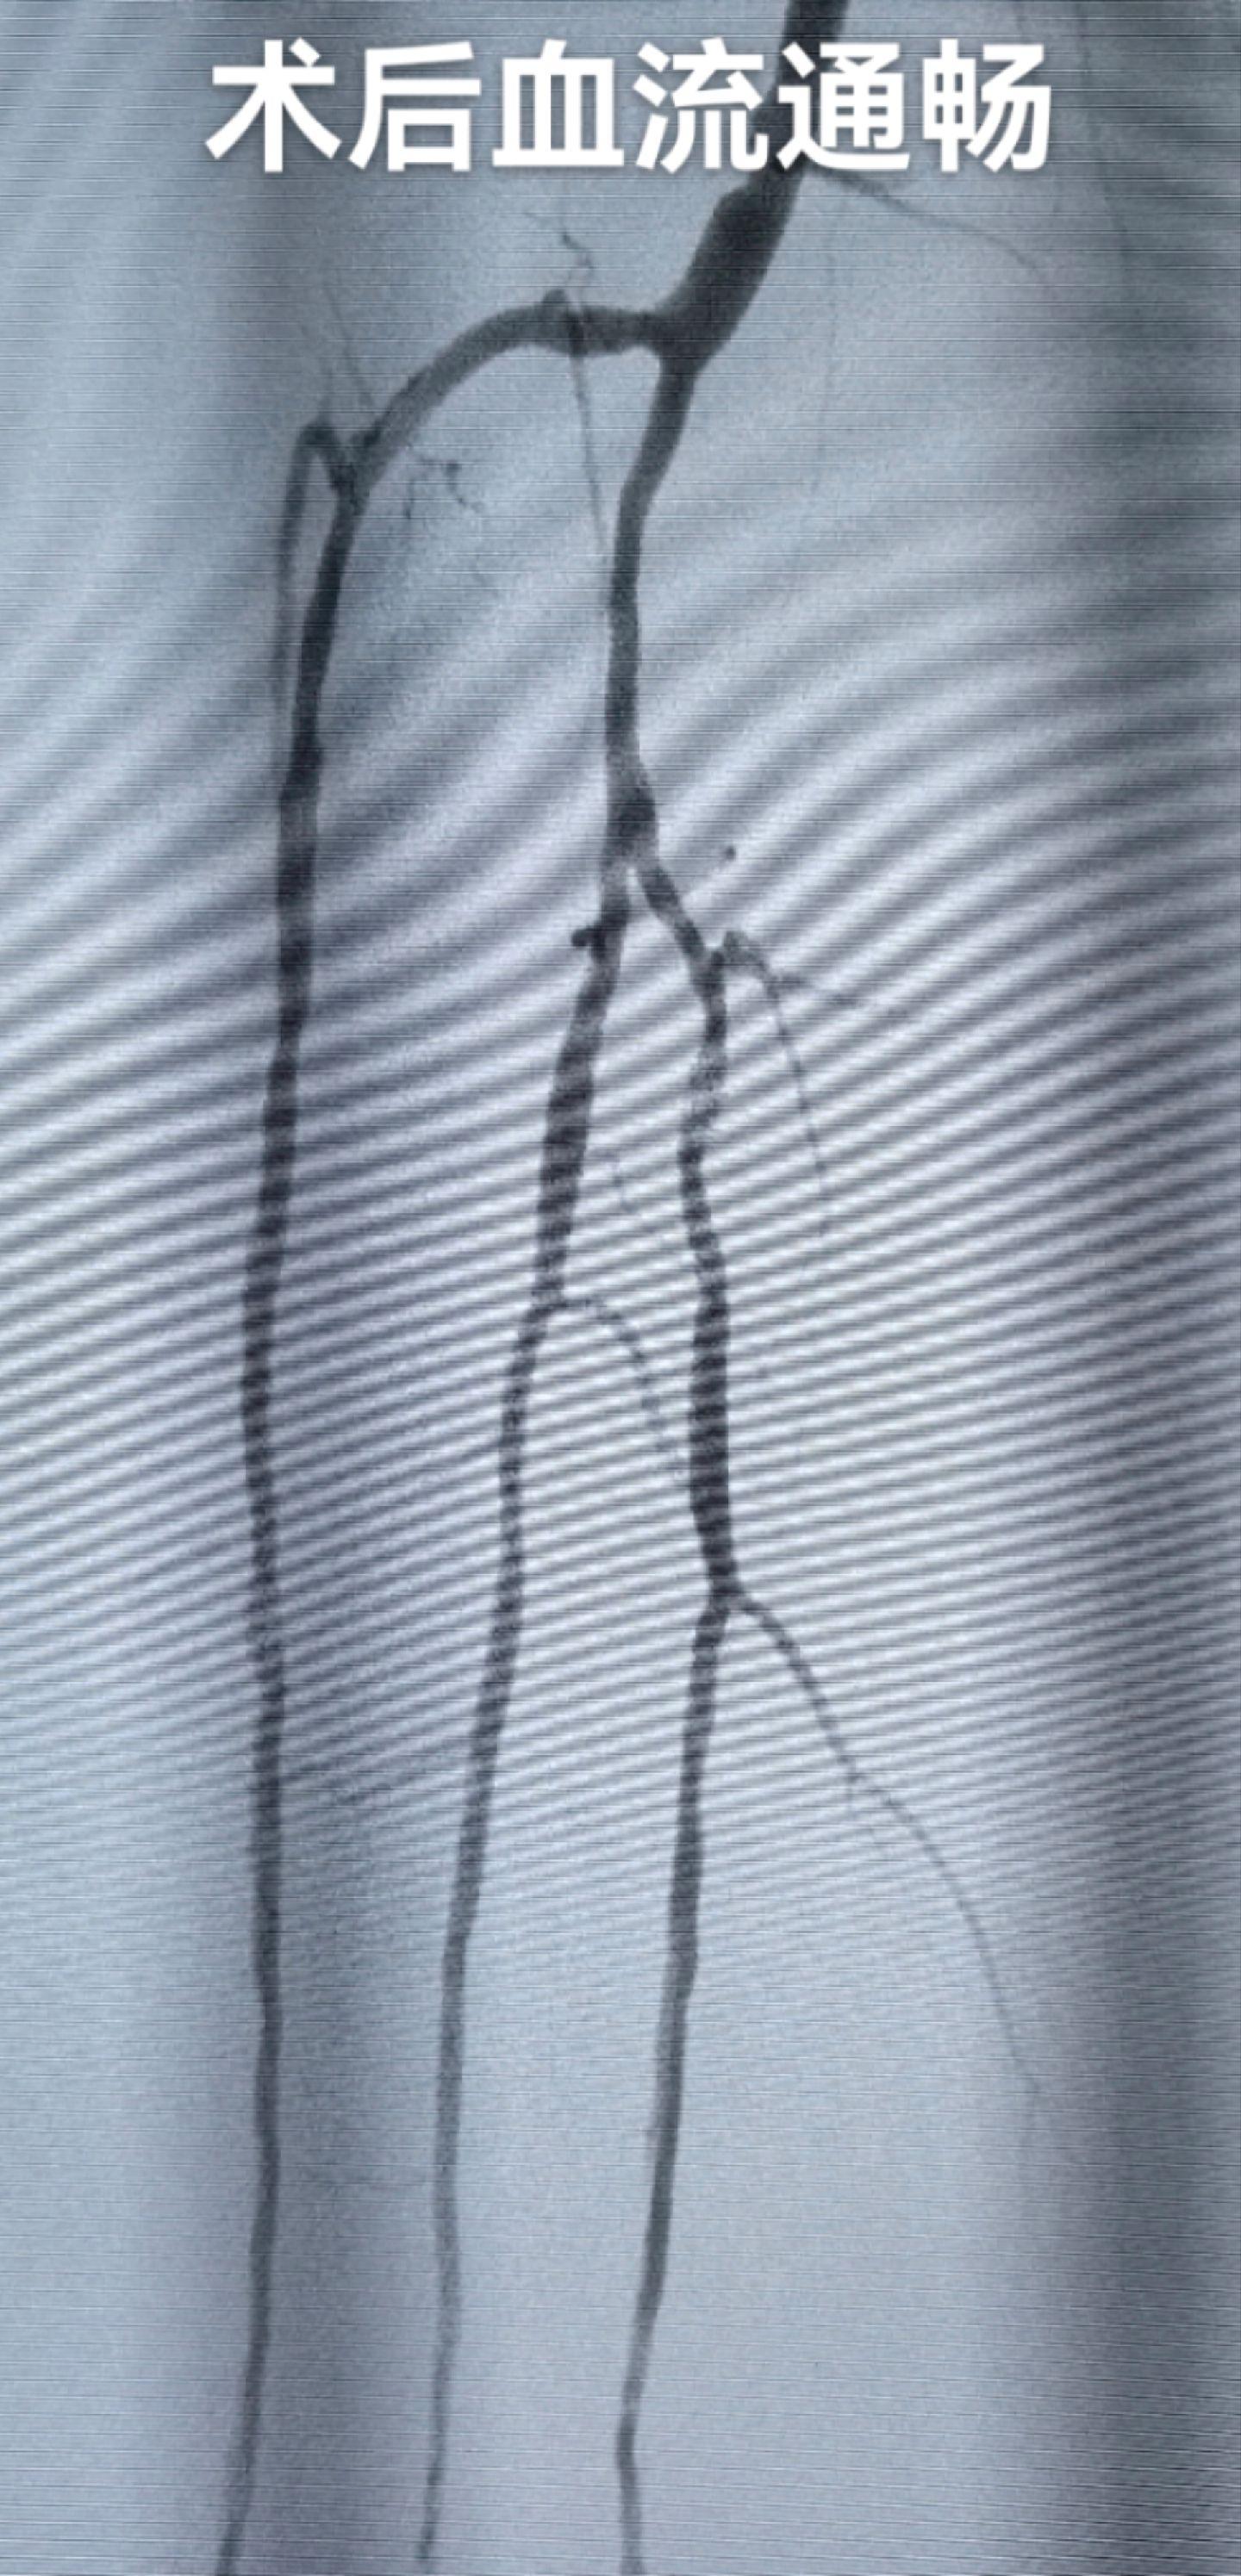

糖尿病足,反复下肢溃疡,膝下三条血管全部开通,保证血流,促进创面愈合